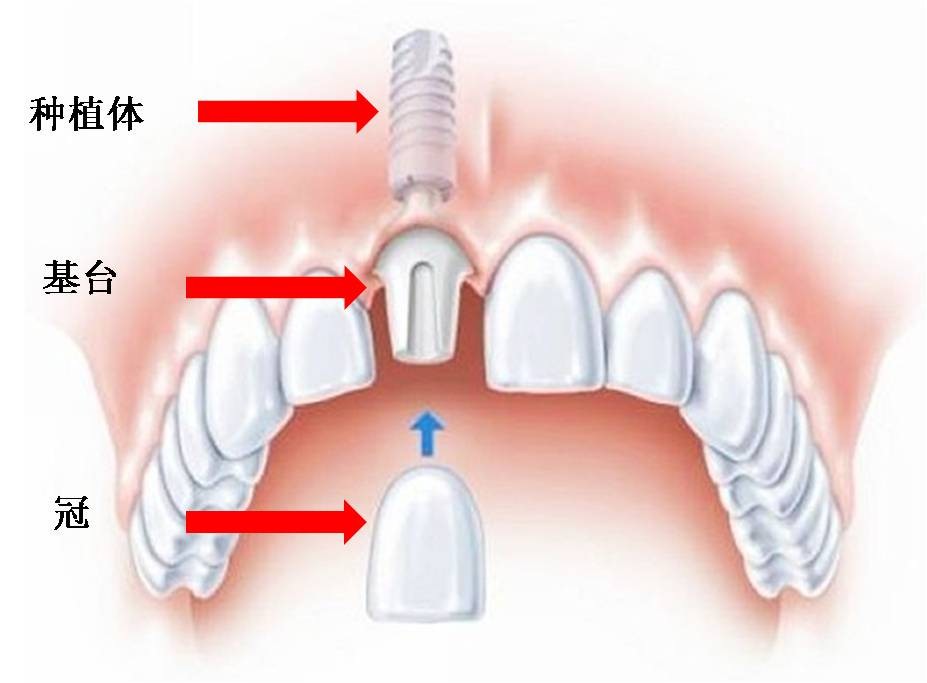

(一)种植义齿的基本组成结构:1.、种植体:是植入骨内的部分,目前流行的仍是预制件,不同厂家制作的种植体在形态、长度、直径、表面处理等不尽相同;2、基台:是种植体穿过软组织的部分,通常用螺丝将它固定在种植体上;3.、上部结构:指修复体通常所具有的冠、桥、支架、附着体等结构。与常规义齿相比,种植义齿可通过标准预制的构件更方便、更精确地通过基台将修复体与种植体相连接。